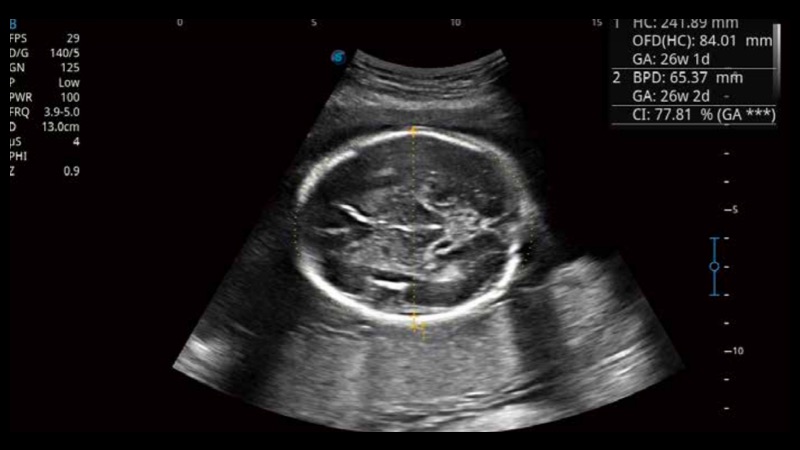

S-Fetus基于大數(shù)據(jù)深度學(xué)習(xí)算法,能夠幫助您在產(chǎn)前篩查過(guò)程中智能識(shí)別胎兒標(biāo)準(zhǔn)切面、自動(dòng)測(cè)量并錄入報(bào)告。一個(gè)按鍵,即可智能、精準(zhǔn)、高效地獲取胎兒生理指標(biāo),極大簡(jiǎn)化您的產(chǎn)科檢查操作。

可快速對(duì)產(chǎn)科掃查切面完成胎兒生理學(xué)參數(shù)的自動(dòng)測(cè)量,減少操作者按鍵次數(shù),大幅提升檢查效率。

自動(dòng)識(shí)別頸項(xiàng)透明層并獲得NT值,為早孕胎兒畸形篩查提供有效測(cè)量工具,提高診斷效率和診斷信心。